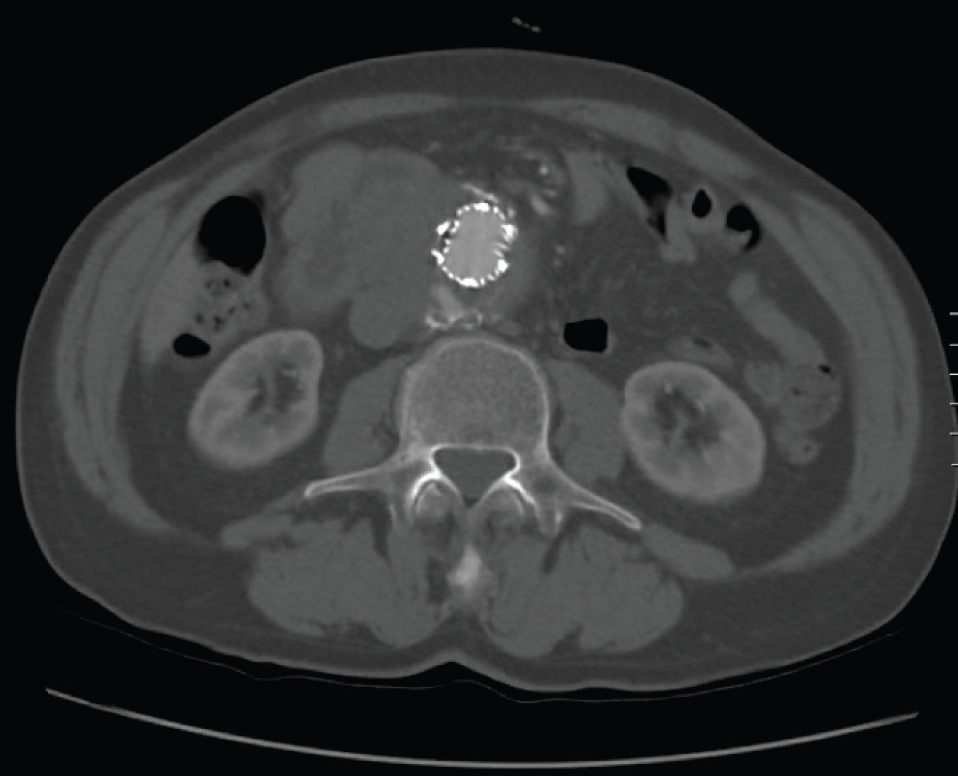

Type II endoleak demonstrated by (A) contrastenhanced computed Radiology Endoleak Types This phenomenon has been coined endoleak (el) by white et al. Type i endoleaks can be subdivided into three further categories: Each type has a different cause. Type iia endoleaks have greater propensity to spontaneously resolve than type iib, which are more complex and difficult to treat (. There are five endoleak types. 3 in this chapter, the different types. Radiology Endoleak Types.